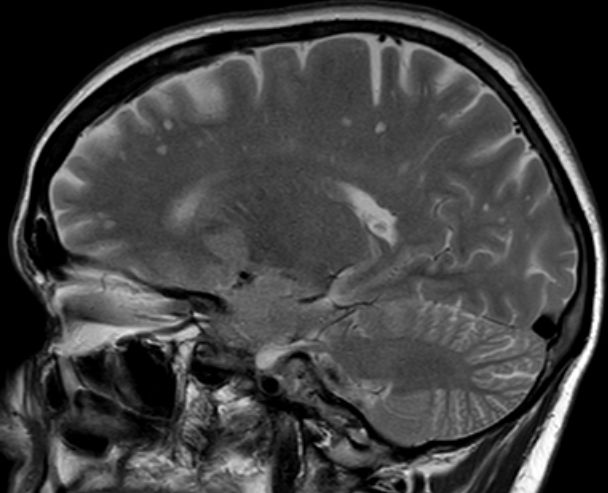

| große zystische Hirnmetastase | asymptomatisches Adenokarzinom des linken

Hauptbronchus mit primärer Hirnmetastase![]() ![]() |